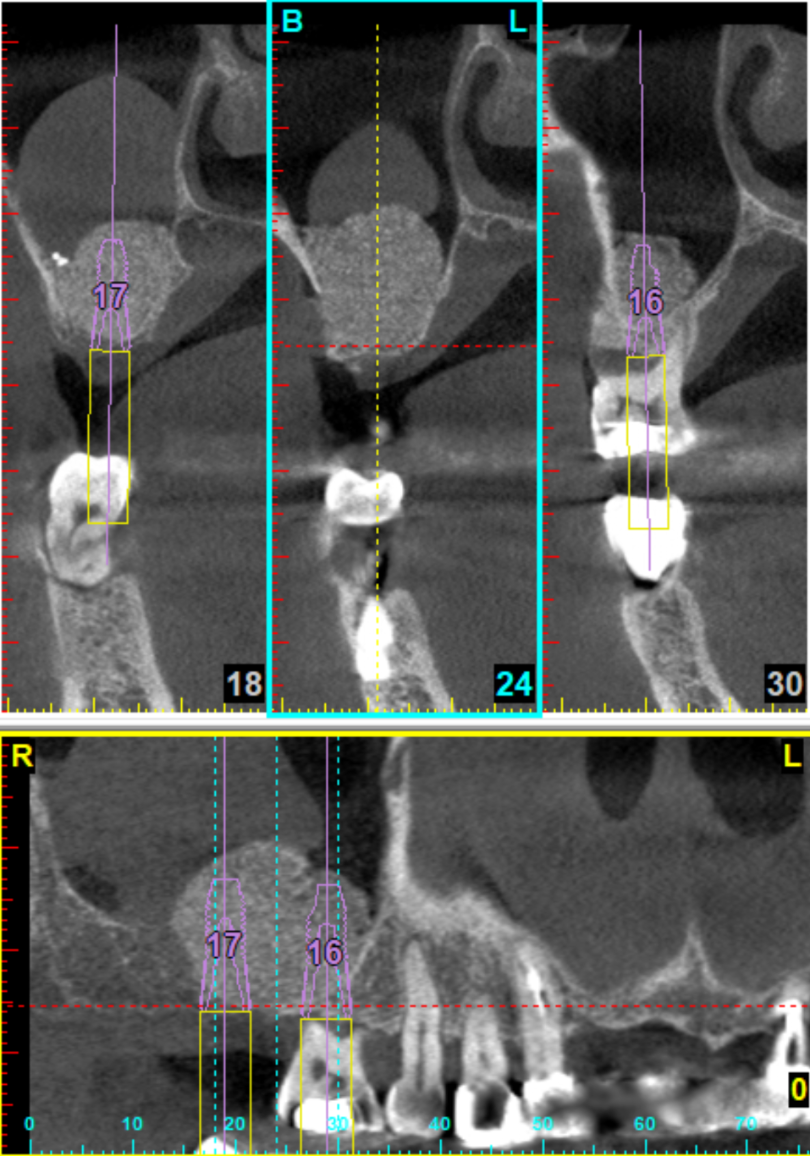

例如,一台開窗式鼻竇增高手術,能看好X光片與電腦斷層,腦中多次模擬手術過程,從切線設計、開窗位置、如何翻鼻竇膜、什麼位置有大血管、如何病人不在眼前,就可以先知道鼻竇內的高低起伏、器械需要準備哪些、有可能遇到什麼突發狀況、有什麼退路。這些都要想清楚。

十年來,我習慣每次開窗手術,都會親手繪製開窗所需要知道的刻度。骨頭高低起伏、牙根走向、血管位置、甚至有時候還會註記側窗骨質厚度等。當然也可以把電腦斷層的資料列印出來。

自己比較喜歡手繪,因為花個十分鐘,拿個鉛筆與橡皮擦,問自己一個問題:「什麼是最重要的資訊?」然後畫出最重要的幾個位置與刻度,相對位置與比例。透過親自手繪,比起列印斷層,來得更有臨場感,這也是手術前模擬的一環。

到手術當天,手繪圖就直接貼在旁邊,考試嘛,帶個小抄才不會答不出來啊~~

像是這個案例,預計只需要植第二大臼齒,但是為了以後隔壁鄰牙可能換成植體,就一併做鼻竇增高了。手術做多了,開窗愈開愈小,只有4mm x 10mm 大小。翻完了,要放骨粉,新買的直徑4.5mm bone graft syringe 還放不進去,應該要買更小的(笑)

這也是我第一次嘗試在自然牙底下增高鼻竇,運氣不錯,自然牙底下的鼻竇質地平緩,只有顎側牙根稍有起伏,這也事先在3D模擬就知道,所以翻膜過程也不會感到驚訝與挫折。